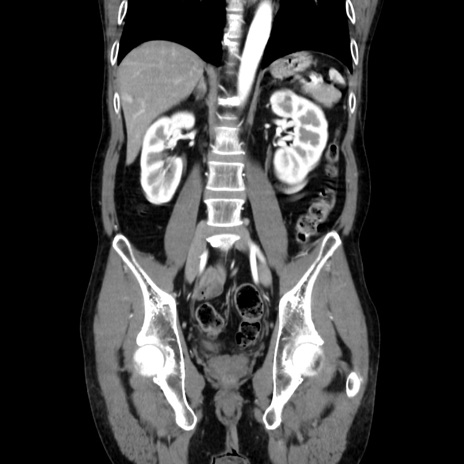

症例37(冠状断像)

【症例】40歳代 男性

【主訴】腹痛

【現病歴】4時間ほど前に電車に乗車中に臍部上より腹痛出現。徐々に増悪し起立困難となり、救急外来受診。生ものは数日食べていない。今朝お雑煮を食べた。

【身体所見】BT 36.8℃、BP 117/84mmHg、HR 91/min、SpO2 97%、苦悶様、腹部:臍上部広範囲圧痛あり、反跳痛±

【データ】WBC 8100、CRP 0.03